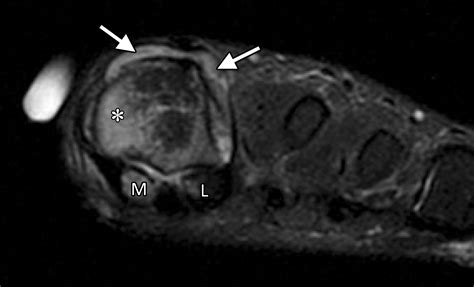

• Order imaging tests, such as X-rays, MRI, or CT scans, to visualize the joint and surrounding structures.